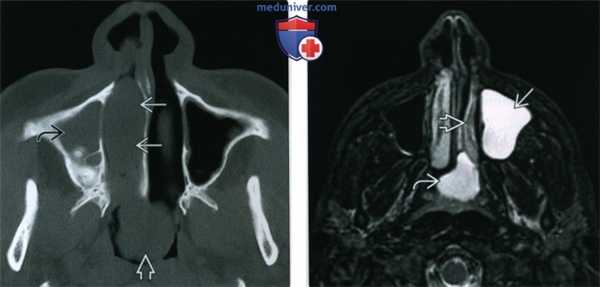

(Слева) При корональной «костной» КТ у девочки 14 лет с муковисцидозом (МВ) определяются типичные признаки ПНП, в т.ч. снижение пневматизации ячеек решетчатой кости справа за счет полиповидного материала, распространяющегося также в полость носа, и доброкачественное ремоделирование костей. Обратите внимание на большое мукоцеле решетчатой кости слева с распространением в орбиту и гипоплазию правой лобной пазухи.

(Справа)При аксиальной «костной» КТ у пациента с МВ визуализируется крупный полип в полости носа справа, связанный со средней носовой раковиной. Выраженная гипоплазия основных пазух часто наблюдается при МВ.